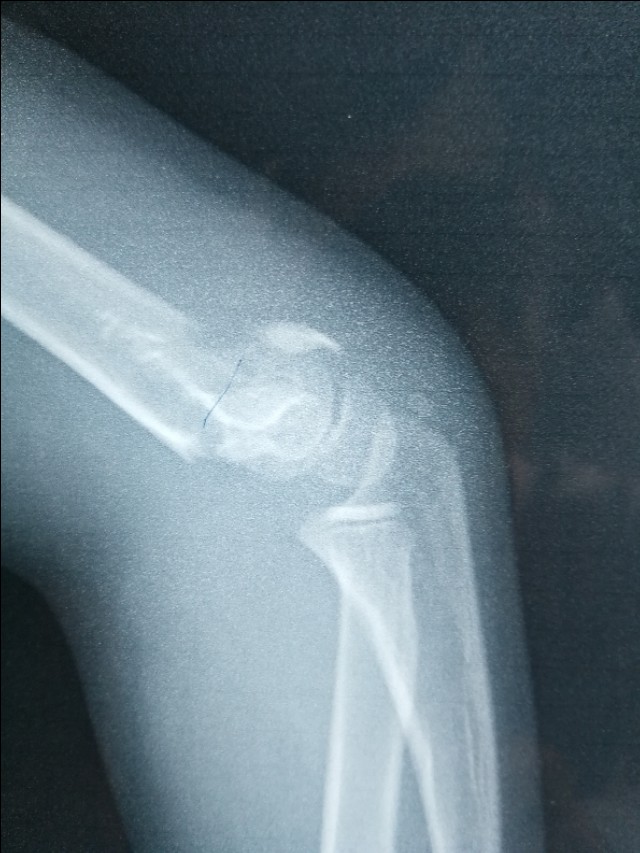

例一:肱骨髁上闭合复位,外固定。几乎解剖对位